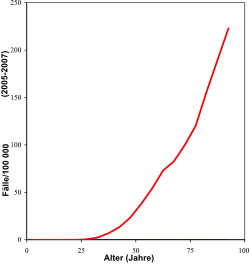

In Deutschland ist das Mammakarzinom mit einem Anteil von 32 % aller Krebsneuerkrankungen die häufigste Krebserkrankung bei Frauen. Das Lebenszeitrisiko wird mit 12,9 % angegeben, d. h. etwa jede achte Frau erkrankt im Laufe ihres Lebens an Brustkrebs.[2] Dies sind in Deutschland etwa 71.900 Neuerkrankungen pro Jahr (2019) oder 171 Fälle pro 100.000 Einwohner und Jahr.[3]

Die Weltgesundheitsorganisation (WHO) gab zum Weltkrebstag im April 2021 bekannt, dass im Jahr 2020 weltweit 19,3 Millionen Menschen an Krebs erkrankten. Als häufigste Krebsart sei Brustkrebs registriert worden, gefolgt von Lungenkrebs. Die Zahl von derzeit rund 20 Millionen Krebs-Neuerkrankungen könnte laut WHO bis 2040 auf etwa 30 Millionen weltweit ansteigen. Für Deutschland prognostizierte die Deutsche Krebshilfe einen Anstieg auf rund 600.000 Krebsfälle im Jahr 2030.[4] Auf Basis von aktuellen Erkrankungszahlen und der erwarteten demografischen Entwicklung haben Wissenschaftler der Internationalen Agentur für Krebsforschung (IARC) und von anderen Instituten im Fachmagazin The Breast eine Prognose für die globale Häufigkeit der Erkrankung aufgestellt: Bis 2040 werde die Krankheitslast weiter zunehmen. Die Autoren gehen dann von über drei Millionen Neuerkrankungen (+40,8 % im Vergleich zu 2020) und einer Million Todesfällen (+51,9 %) pro Jahr aus – allein schon wegen der wachsenden und immer älter werdenden Weltbevölkerung.[5]

Bei internationalen Vergleichen muss die unterschiedliche Altersverteilung der nationalen Bevölkerungen berücksichtigt werden. Die nach dem sogenannten Europastandard (ESR) altersstandardisierte Inzidenz (Neuerkrankungsrate) lag in Deutschland im Jahr 2010 für Frauen bei 119,6/100.000.[3] Die brustkrebsbedingte Sterberate (Mortalität) betrug im selben Jahr altersstandardisiert 24,0/100.000 nach dem ESR.[3] Seit 1970 haben sich die Erkrankungszahlen verdoppelt, während die Mortalität eher rückläufig ist.[6]

Brustkrebs ist weltweit die häufigste invasive Tumorerkrankung bei Frauen. Weltweit gibt es nach Schätzungen der WHO (2003) etwa 1.050.000 neue Erkrankungsfälle pro Jahr, davon 580.000 in den Industriestaaten. Vergleichsweise seltener ist die Erkrankung in Afrika und Asien. Weltweit starben 1998 circa 412.000 Frauen an Brustkrebs, was 1,6 % aller gestorbenen Frauen entspricht.[7] Damit ist Brustkrebs weltweit die häufigste krebsbedingte Todesursache bei Frauen. In der westlichen Welt ist Brustkrebs bei Frauen zwischen dem 30. und 60. Lebensjahr die häufigste Todesursache überhaupt.

In Deutschland schätzt man etwa 17.460 brustkrebsbedingte Todesfälle pro Jahr[3] und in den Vereinigten Staaten etwa 40.200. In Deutschland beträgt die durchschnittliche Fünfjahresüberlebensrate zurzeit 86–90 %.[3][8] Während jedoch in den reichen Ländern die Sterberate sinkt, ist sie in den ärmeren Ländern hoch. Dies hängt zum einen mit der immer höheren Lebenserwartung zusammen, zum anderen mit den schlechteren diagnostischen und therapeutischen Möglichkeiten in den ärmeren Ländern. WHO-Angaben zufolge starben 2007 etwa 72 Prozent aller an Krebs erkrankten Menschen in Ländern mit mittlerem und niedrigem Einkommen.[9] Dennoch gab es 2013 in den Vereinigten Staaten das Phänomen von steigenden Brustkrebsraten bei jungen Frauen, für die es bisher keine zufriedenstellende Erklärung gibt.[10]